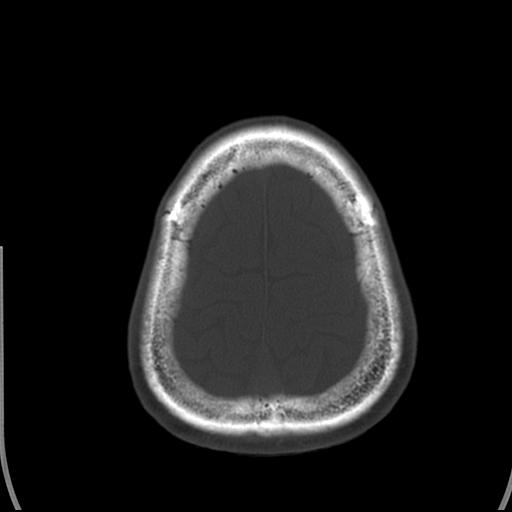

标题: CT25435:头皮下高密度影???

头皮下高密度结节影???临床上在老年男性比较常见。大家看看是什么?成因是? 本例患者,男性,51岁。外伤来诊。无染发史及发根植入史。

你说的是皮肤上的高密度占性影吧,没见过,不过我想一是没事,二是怎么来的可能是有点不全钙化的意思吧,没见过所以不知道

皮下钙化点

没见过,可能为毛囊钙化。